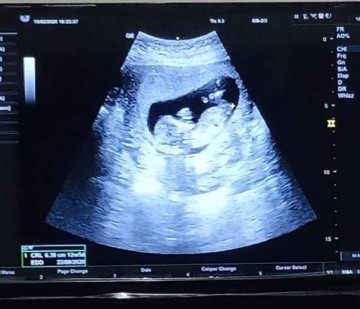

ใครเห็นเหมือนน้องยิ้มบ้าง

คุณแม่ท่านไหนกำหนดคลอด เดือน สิงหาคม บ้าง

22 สิงหาคม เหมือนกันค่ะ

กำหนดคลอดน้องแฝด12 สิงหาคะ

17 สิงหาจ้า ถ้าอยู่ถึงนะ 55555

กำหนดคลอด29สิงหาจ้าา

17สิงหาจ้า 17วีคเเล้วจ้ะ

14สิหาจร้า รู้เพศยังค่ะ

สิงหาเหมือนกันจ้าาาาา

สิงหาคม เพศชายครับผม

กำหนดคลอด 27 สิงหาค่ะ